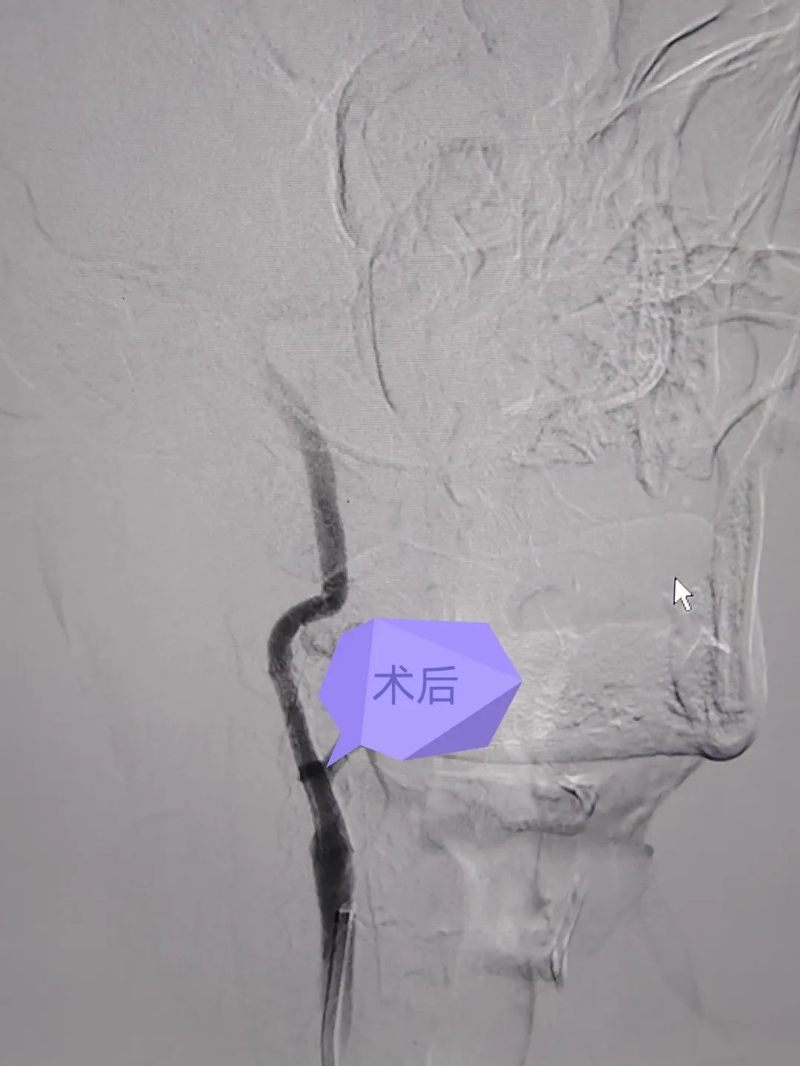

在與家屬充分溝通獲得其同意后,李金星便迅速開展了介入手術。腦血管介入治療是在造影機器照射下通過血管動脈入路進行的微創手術治療,手術創傷小,僅通過2~3毫米的動脈穿刺點完成的微創支架置入手術。介入團隊為患者行急診右側頸動脈支架置入,右側椎動脈支架置入,術后患者癥狀消失,隨后肢體活動自如,精神狀態良好。據家屬描述,術后覺得患者精神許多,反應比以前好了,話也多了,記憶力也改善了,之前血管重度狹窄,大腦供血很差,支架術后,現在癥狀都有改善。

對頸動脈狹窄進行球囊擴張(目的是為了支架能更好地和狹窄血管貼壁),然后醫生把支架精準定位到頸動脈狹窄處釋放,打開狹窄血管(如下圖)。